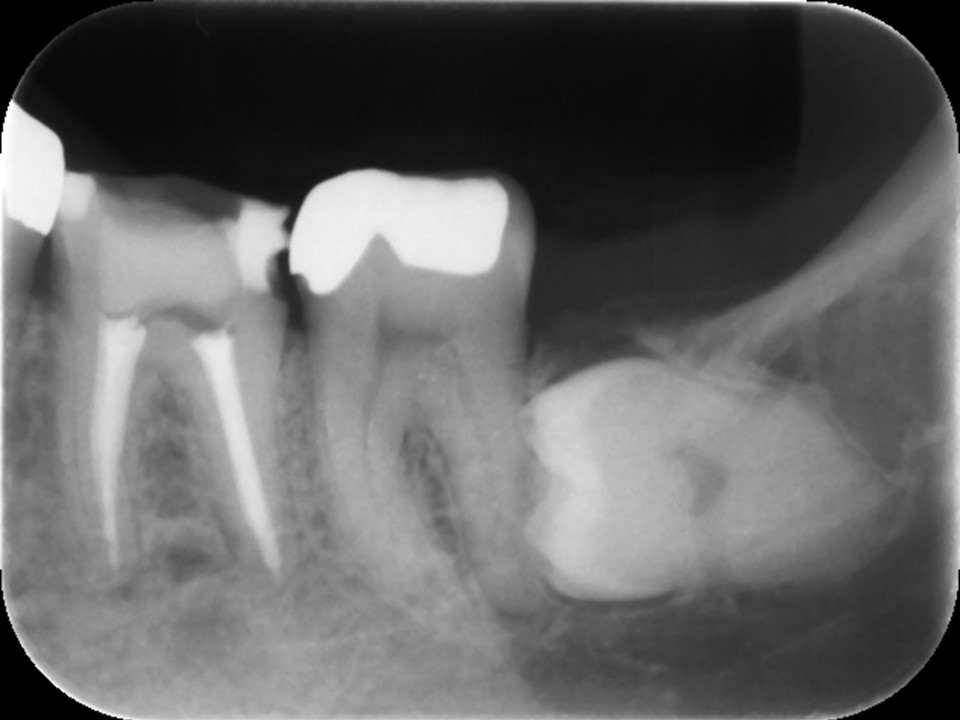

初診時レントゲン。他院にて根管治療を数か月行っているが痛みが続いていると訴えて来院。根管内には依然に詰めた薬がまだ残っているように見える。根尖部の骨破壊はほとんど認めない。

再根管治療後レントゲン。多少の違和感はあったものの、根管内部がきれいになり、排膿を認めないことから根管充填(薬を詰めること)を行った。根尖部までしっかりと薬が詰まっているのが分かる。歯根の内部がきれいな状態であれば、歯科医にはそれ以上出来ることはない。悪戯に弄り過ぎてはいけない。